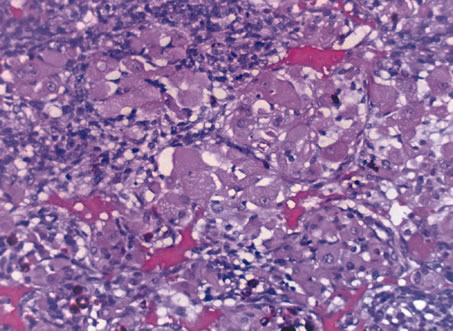

In 1931, Callender classified uveal melanomas based on cytologic features.166 He described six groups, four of which were based on cytology and two on other histologic features. The groups based on cytology were tumors composed of (1) spindle-A cells, (2) spindle-B cells (Fig. 26), (3) epithelioid cells (Fig. 27), (4) a mixture of epithelioid and spindle cells (Fig. 28). The fifth group consisted of tumors with a fascicular pattern, and the the sixth group was composed of tumors that could not be classified in the other groups because of extensive necrosis (Fig. 29). Spindle cells are described as fusiform and arranged in tightly cohesive bundles. The plasma membranes of the cells are indistinct and have a syncytial appearance. Spindle-A cells have a slender nucleus with fine chromatin and a longitudinal fold in the nuclear envelope that gives the appearance of a line. Spindle-B cells have a slightly plumper nucleus, coarser chromatin, and a more prominent and eosinophillic nucleolus. Epithelioid cells are larger and more pleomorphic. They have an abundant glassy cytoplasm, a polyhedral shape, and a distinct cell border and are less cohesive. Epothelioid cells tend to have a larger and rounder nucleus than the other types, with a more angular nuclear envelope and irregular indentations. The chromatin is coarse and marginated, and large eosinophillic nucleoli are present.

Fig. 29. Choroidal melanoma. Necrotic tumor cells are mixed with melanophages. (Hemotoxylin-eosin ×200.)